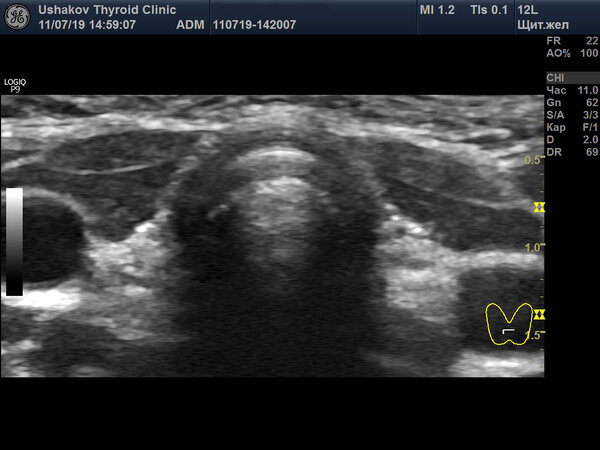

- По данным УЗИ, сама щитовидная железа имела нормальное строение и размеры.

Данные УЗИ однозначно свидетельствовали: щитовидная железа у девочки была сформирована нормально и была функционально полноценной. «Легкая степень» гипотиреоза указывала на то, что у ребенка был запас собственных гормонов, который интенсивно расходовался в борьбе за выживание в условиях кислородного голодания. Повышение ТТГ было компенсаторной, а не патологической реакцией.

Врач, сфокусированный лишь на снижении ТТГ, продолжал тактику «лечения анализа», не корректируя дозу. В результате произошло то, что и должно было произойти: собственная щитовидная железа, получая сигнал, что гормонов в крови и так избыток, постепенно снизила, а затем и практически прекратила свою активность. Начался процесс её атрофии. К пяти годам объем железы, который в норме должен составлять 2.5-3 мл, уменьшился до 0.4-0.7 мл.